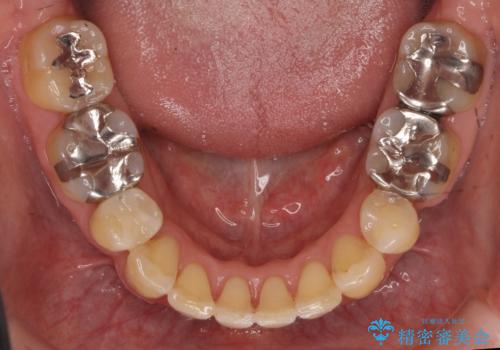

40代の矯正 出っ歯、歯のがたがた

- 40代になってから、矯正治療で前歯をきれいに並べられる事を知り、矯正を希望されました。

奥歯のかみ合わせのずれと、前歯のがたつきがありました。

上下左右の小臼歯を抜歯しています。

叢生も著しく、少し年齢が上がってからの矯正治療となり、結果ブラックトライアングルが出てしまいましたが、並びの改善で非常に満足していただけました。